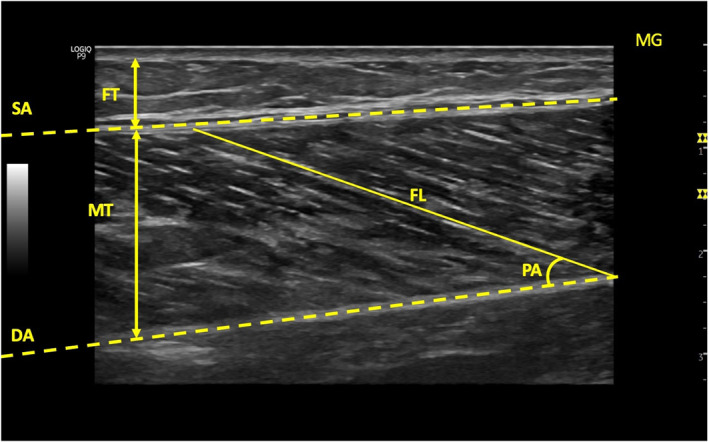

Methods: Fifty women with knee OA (mean age = 52.11 ± 4.96 years, mean Body mass index (BMI) = 30.94 ± 4.23 kg/m2) and 50 healthy women as a control group (mean age = 50.93 ± 3.78 years, mean BMI = 29.06 ± 4.82 kg/m2) were included in the study. Ultrasonography was used to evaluate knee and ankle muscles architecture and femoral cartilage thickness. The plantar pressure distribution was evaluated using the Digital Biometry Scanning System and Milleri software (DIASU, Italy). Static foot posture was evaluated using the Foot Posture Index (FPI), and pain severity was assessed using the Visual Analog Scale.

Results: The OA group exhibited lower muscle thickness in Rectus Femoris (RF) (p = 0.003), Vastus Medialis (VM) (p = 0.004), Vastus Lateralis (p = 0.023), and Peroneus Longus (p = 0.002), as well as lower Medial Gastrocnemius pennation angle (p = 0.049) and higher Fat thickness (FT) in RF (p = 0.033) and VM (p = 0.037) compared to the control group. The OA group showed thinner femoral cartilage thickness (p = 0.001) and higher pain severity (p = 0.001) than the control groups. FPI scores were higher (p = 0.001) in OA group compared to the control group. The plantar pressure distribution results indicated an increase in total surface (p = 0.027), total load (p = 0.002), medial load (p = 0.005), and lateral load (p = 0.002) on dominant side in OA group compared to the control group.